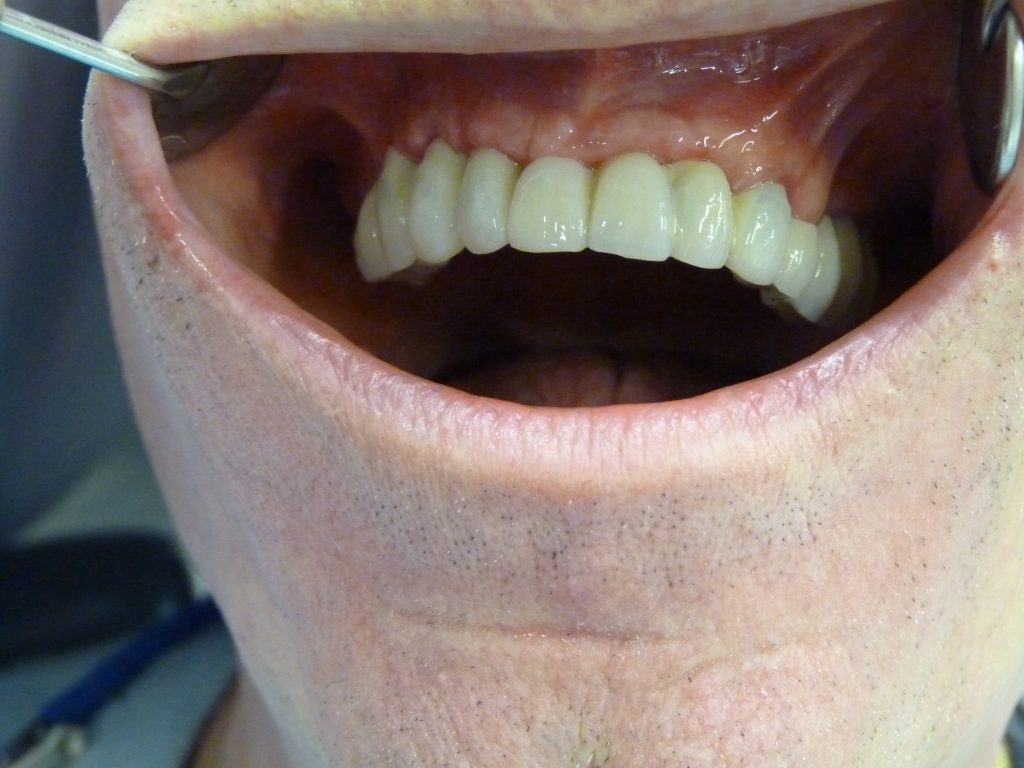

BRIDGE CERAMIQUE MIXTE DENTS NATURELLES ET IMPLANTS DENTAIRES

BRIDGE CERAMIQUE MIXTE DENTS NATURELLES ET IMPLANTS. CONTROL 3 ANS.   Pose d’un bridge ceramo metallique de 12 dents sur des implants dentaires et des dents naturelles. Au niveau des implants, intégration tissulaire parfaite grâce aux connexions implantaires supra-gingivale.   Chirurgien: Dr. Thierry Hascoet Prosthodonte: Dra. Yanira Peña Laboratoire: SIVP Barcelone